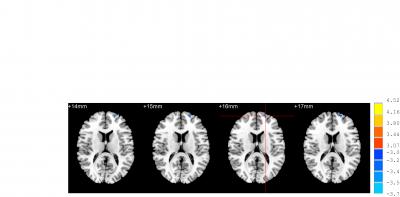

image: Decreased activity was observed in left Brodmann area 10 during sham acupuncture. Blue represents inhibition. view more

Both acupuncture at Waiguan (SJ5) and sham acupuncture can activate/deactivate several brain regions in patients with ischemic stroke, but there are some difference in Brodmann areas 4, 6, 8, Brodmann areas 7, 39, 40, Brodmann areas 18, 19, 22 and Brodmann areas 13, 24, 32, 28. Most studies addressing the specificity of meridians and acupuncture points have focused mainly on the different neural effects of acupuncture at different points in healthy individuals. Dr. Ji Qi and co-workers from School of Traditional Chinese Medicine, Southern Medical University in China examined the effects of acupuncture on brain function in a pathological context, and compared the effects between Waiguan and sham points in 16 patients with ischemic stroke. Compared with sham acupuncture, acupuncture at Waiguan in stroke patients inhibited Brodmann area 5 on the healthy side. These findings, published in the Neural Regeneration Research (Vol. 9, No. 3, 2014), indicated that the altered specificity of sensation-associated cortex (Brodmann area 5) is possibly associated with a central mechanism of acupuncture at Waiguan for stroke patients.